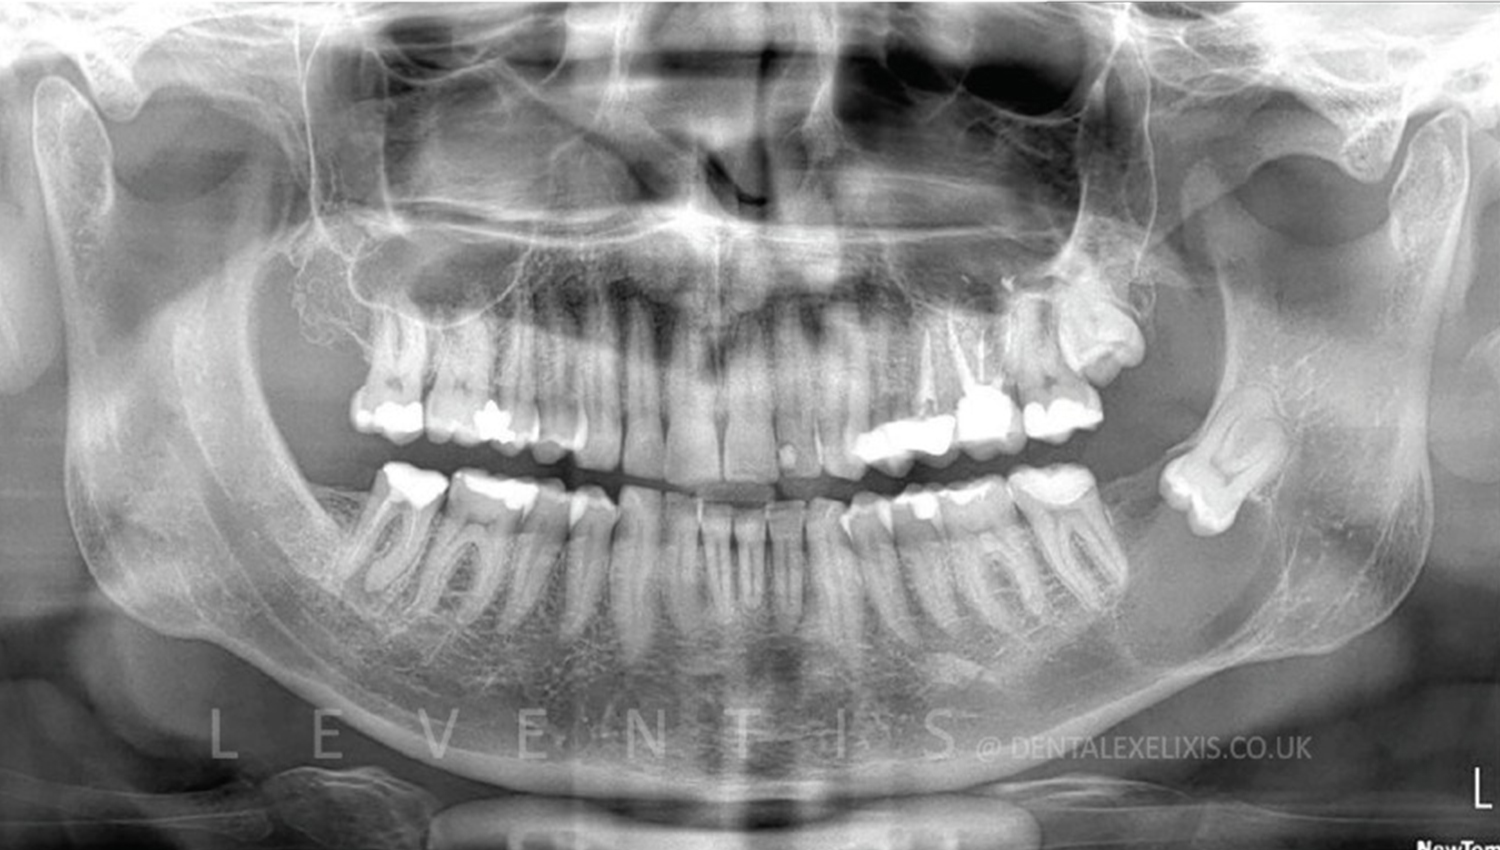

1. Initial radiological view.